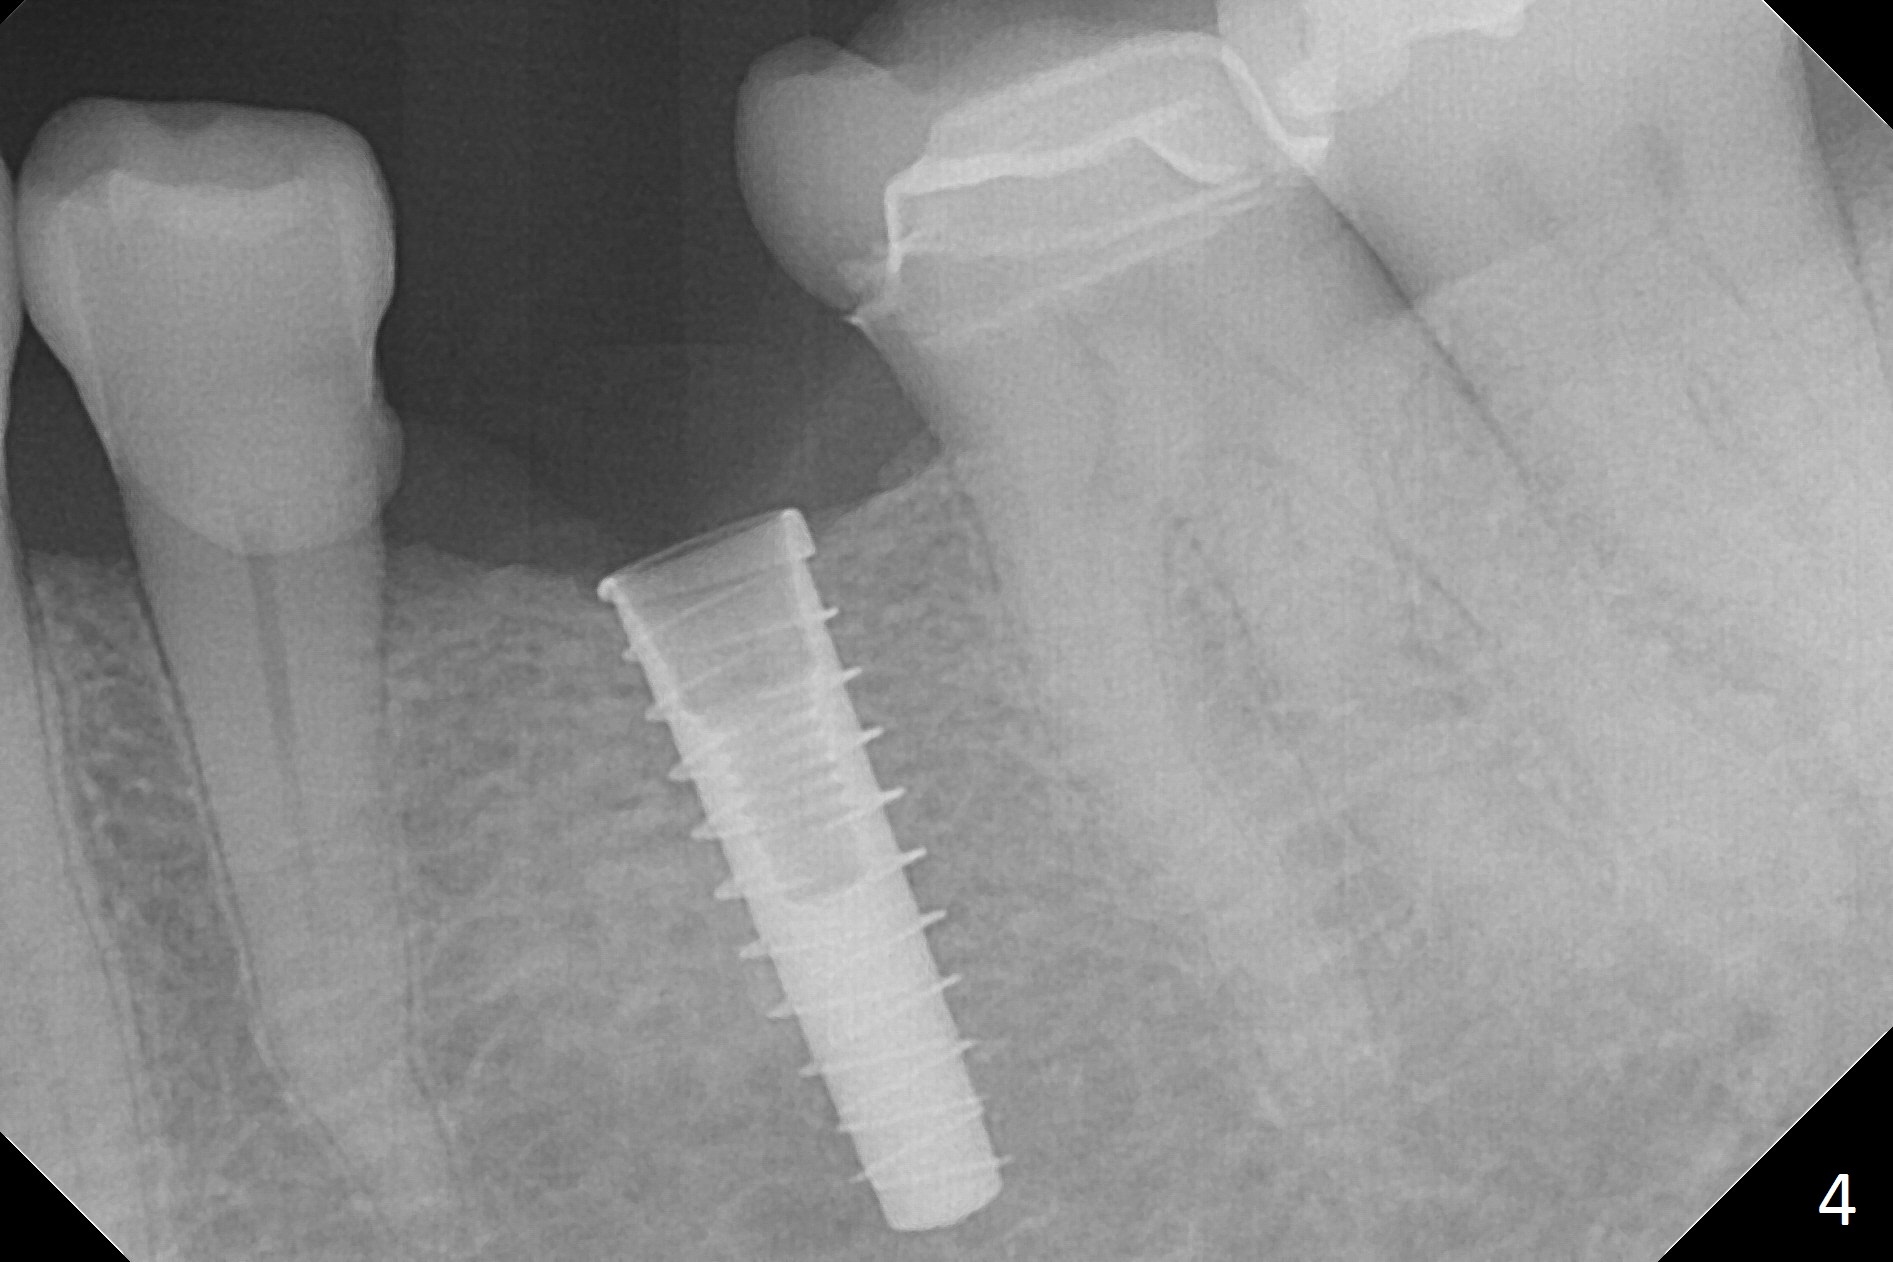

Initial osteotomy with 1.6 mm drill for 11 mm seems to be distal (Fig.1). The trajectory should be changed as shown by the black line in Fig.2; the drawback would be close to the Mental Loop (red line). Fortunately the trajectory is changed, but not so much as to be close the Loop when a 4x11 mm dummy implant is placed (Fig.3). When a 4x13 mm IBS is placed with 46 Ncm, there is clearance from the Loop (Fig.4-6). In fact there is no postop paresthesia. The main point is no block anesthesia. Infiltration anesthesia is administered with 34 mg Xylocaine with 17 mcg Epinephrine. The patient experiences dull pain when the implant is placed (Fig.4-6). After further anesthesia with 68 mg Septocaine, 17 mcg Epinephrine, the implant is torqued for a few turns (still with some discomfort). Finally autogenous bone with Osteogen is placed around the implant following placement of a 4.5x4(2) mm abutment. To reduce anxiety, a shorter implant should have been used. The patient complains of cold sensitivity in the lower left quadrant 4 months postop (Fig.7): the implant apparently close to the Mental Loop. Without an immediate provisional, the gingiva around the abutment is healthy.